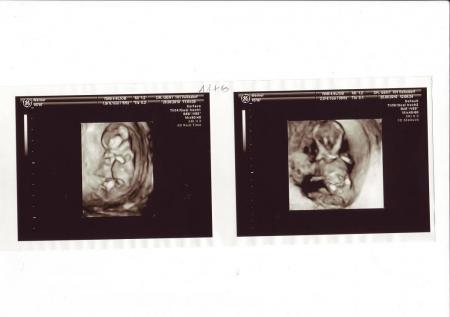

Hallo ihr Lieben, bin wieder da. Das Baby ist super gesund, völlig zeitgerecht entwickelt und sehr lebendig. Die NFM war auch so wie es sein soll. Der Magen und die Blase war gefüllt, keine Hasenschate, Trisomie 21 ist ausgeschlossen, da die Nasenknochen vorhanden sind und die NF zwischen 0.9 und 1,2 cm ist. Bei über 2 cm müssten weitere Untersuchungen gemacht werden. Und: Es wird zu 80 % ein Junge. War gleich zu sehen. Könnte aber auch eine angeschwollene Klitoris sein, was nicht sehr warscheinlich ist. Ein bißchen enttäuscht bin ich schon. Hatte mir nach 2 Jungs so sehr ein Mädchen gewünscht. Aber das ist nunmal so und ich freue mich trotzdem sehr. Nächster Termin ist der 23.09. Mein Geburtstag. Passt doch gut, oder. Und hier die 3D Bilder. GlG

2. Bild